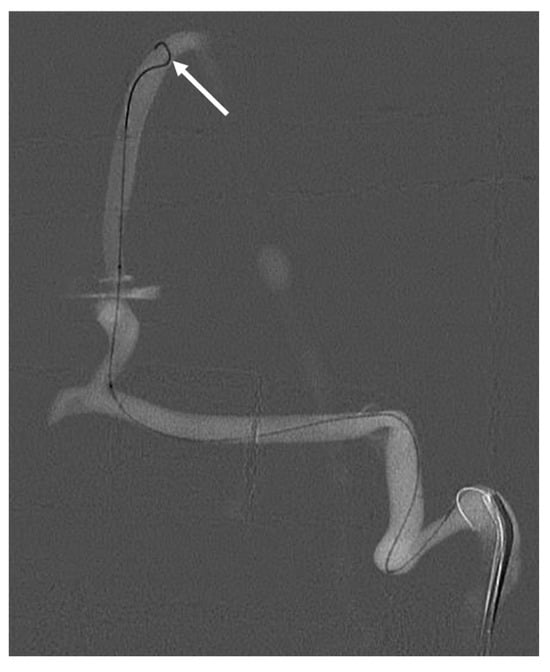

The DSA images show a well-perfused venous system that can be used as a roadmap for catheter navigation. The venous system was then probed under X-ray guidance. Figure 5 shows catheterisation of the superior sagittal sinus, the transverse sinus, the sigmoid sinus and the internal jugular vein. The microcatheter could be successfully navigated by the physician to the throttle.

Figure 5.

Catheterisation of the venous system highlighted by a white arrow.